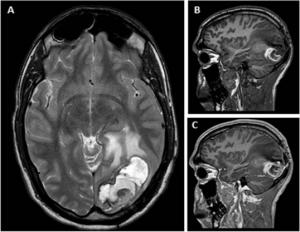

The case involves a 28-year-old male who had undergone SRS for a brain AVM. A full ten years after treatment, the patient developed a cystic lesion—a fluid-filled sac within brain tissue—which initially caused no symptoms but slowly enlarged over time. Eventually, a surgical procedure was performed to drain the cyst. However, in the years that followed, the patient experienced a recurrence, this time presenting as a chronic encapsulated expanding hematoma (CEEH)—a rare condition in which a blood clot continues to grow within a fibrous capsule, exerting pressure on surrounding brain tissue. This development required a more invasive surgical procedure: lobectomy, or the removal of the affected portion of the brain.

Upon further examination, the researchers discovered that the initial cyst had contained an angiomatous nodule—a small, benign mass composed of blood vessels—that had been overlooked during the first surgery. It is believed that this vascular nodule may have been the source of slow, ongoing bleeding, which ultimately led to the transformation of the cyst into a hematoma.

The findings also challenge existing surgical treatment strategies for managing late-onset cysts, particularly those that exhibit contrast-enhancing nodules—areas that light up on MRI when contrast dye is used, indicating abnormal or active tissue. In many cases, cyst drainage alone may seem sufficient, but this case suggests that such an approach could allow underlying causes—like angiomatous nodules—to go untreated, increasing the risk of recurrence.

Beyond surgical technique, the authors also emphasize the importance of long-term follow-up for patients who have undergone SRS. In this case, post-treatment imaging had initially shown complete resolution of the AVM. However, more subtle radiation-induced changes were already visible as early as five years after radiosurgery—changes that could have served as early warning signs. These findings reinforce the importance of not relying solely on angiographic resolution to declare treatment success.